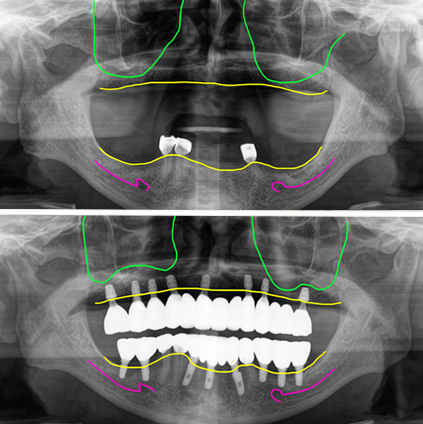

상악동 윈도우 뼈이식 병행식립 수술당일임시치아

수술은 위아래 동시에 진행했습니다. 위쪽에는 양쪽 모두 상악동 부위에 뼈가 부족해서 뼈이식을 했습니다.

우측부에는 측방으로 접근에서 뼈를 많이 넣는 윈도우방식으로 수술했고, 좌측에서 수직으로 접근해서 리프팅방법으로 간단하게 하는 뼈이식을 진행했습니다.

뼈이식과 함께 임플란트를 식립했고, 뼈이식을 한 부위에서 초기고정이 부족한 부위는 잇몸 속에 임플란트를 두었습니다.

아래 남기는 치아는 보철을 제거한 후 식립한 임플란트와 연결해서 임시치아를 만들어 즉시하중을 시작했습니다.